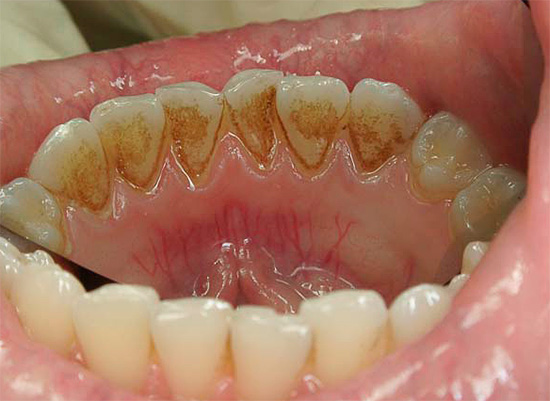

I denti anteriori inferiori, di norma, sono tutti i meno sensibili allo sviluppo della carie e in futuro - pulpite a causa dell'elevato grado di lavabilità della saliva. Poiché la saliva è una sorta di "smalto liquido", è in questo gruppo di denti che i componenti minerali persi (calcio, fosforo) ritornano più rapidamente.

Tuttavia, non bisogna dimenticare che, nonostante tale "fortuna" dei denti anteriori inferiori per quanto riguarda i rischi di sviluppare complicanze della carie (pulpite e parodontite), i denti inferiori sono più inclini a depositare tartaro su di loro proprio a causa della stessa saliva altamente salina ( vedi l'esempio nella foto).